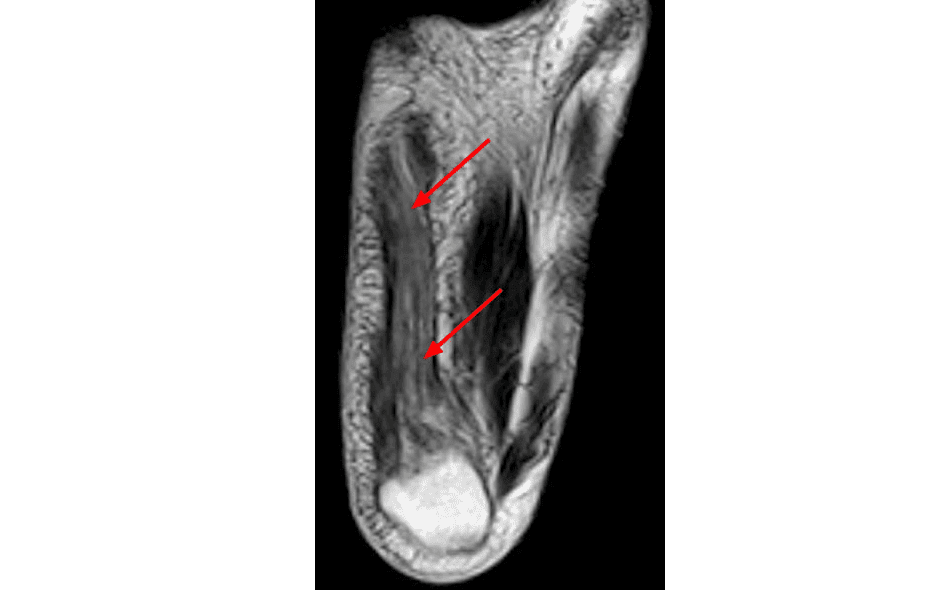

A magnetic resonance imaging (mri) was performed on a normal subject; Bone contusions, osteonecrosis, marrow oedema syndromes, and stress > fractures) > synovial based disorders ( e.g. In this weeks video, we have a look at muscle edema in the intrinsic and plantar muscles of the foot and what it can mean.patreons can access original dicom. The medial muscles of the foot sole have various tasks: Mri and ultrasound have been utilised in the assessment of the plantar intrinsic foot muscles. However, on mri images, no muscular abnormalities were detected. Indications for foot mri scan. First of all they act upon the metatarsophalangeal joint of the big toe, leading to the abduction.

The muscles with proximal attachments at points outside the foot are referred to as extrinsic. Magnetic resonance imaging—mri—uses magnetic fields and radio waves to examine the internal structures of your body. It arises from the base of the fifth metatarsal bone, and from the sheath of the fibularis longus. Top suggestions for foot muscle anatomy mri. Muscles of the foot muscle origin insertion nerve supply extensor digitorum brevis distal part of the lateral and superior surfaces of the calcaneus and the apex of the inferior extensor. However, on mri images, no muscular abnormalities were detected. Mri also allows to determine the course of the healing process and the success of. Mri can be very helpful in order to establish an early diagnosis of charcot foot. Indications for foot mri scan. Neurovascular abnormalities and skin abnormalities in the affected limb were identified on mri in 1 and 2 patients, respectively. At ultrasonography the thickness and csa of the whole muscle of interest was determined. | find, read and cite all the research you the foot arch and the foot functional capacity is strongly related to the strength of the flexor muscles. Mri is particularly useful in visualizing soft tissue lesions that may be compressing a.